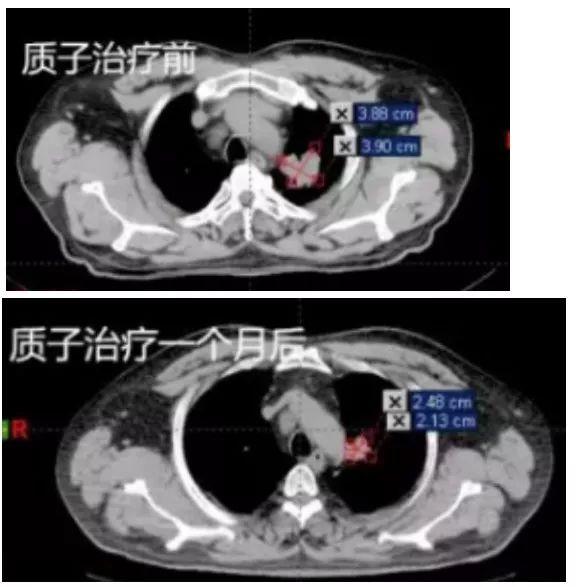

55岁男性,无明显诱因出现走路左偏,左侧上肢抽搐,发作时意识清醒,持续时间约1-2分钟,可自行缓解。PET-CT显示:左肺上叶尖后段肺癌;并右侧顶叶脑转移,在全麻下行“脑转移瘤切除术”,术后症状明显改善。

病理检测无基因突变,术后行化疗2周期,后拟行手术治疗,因肺部肿瘤靠近大血管,不能手术,经专家咨询,行质子放射治疗。质子治疗一个月后,肿瘤体积缩小65%。

质子治疗前后对比CT